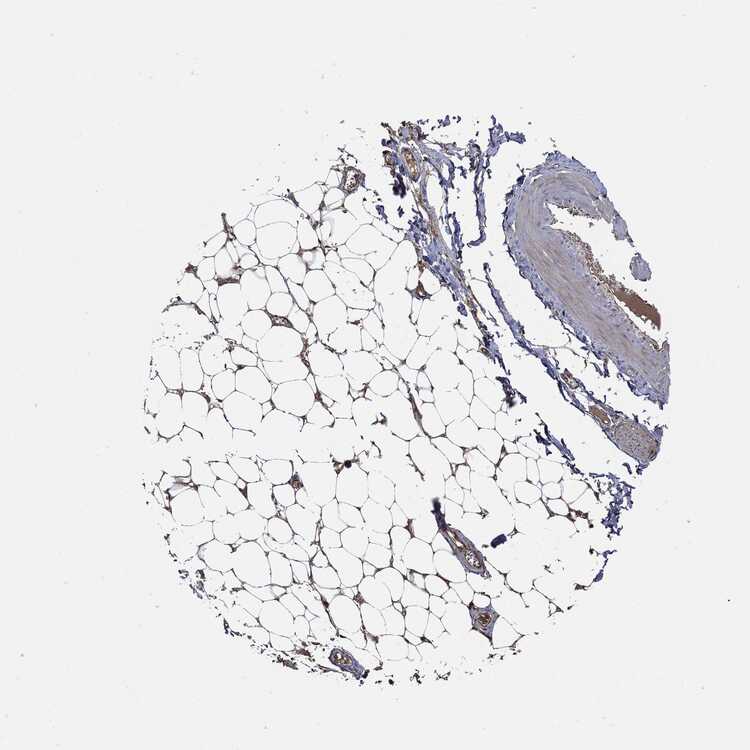

SOFT TISSUE 2 - Antibody stainingi

Antibody staining in the annotated cell types in the current human tissue is reported as not detected, low, medium, or high, based on conventional immunohistochemistry profiling in selected tissues. This score is based on the combination of the staining intensity and fraction of stained cells.

Each image is clickable and will lead to virtual microscopy that enables deeper exploration of all samples and also displays staining intensity scores, fraction scores and subcellular localization as well as patient and tissue information for each sample.

Antibody HPA030419Antibody HPA030420Antibody CAB025196Antibody CAB080286Antibody CAB080287

Chondrocytes Not detectedNot detected---

Fibroblasts Not detectedNot detectedNot detectedMediumLow

Peripheral nerve Not detected-LowMediumNot detected